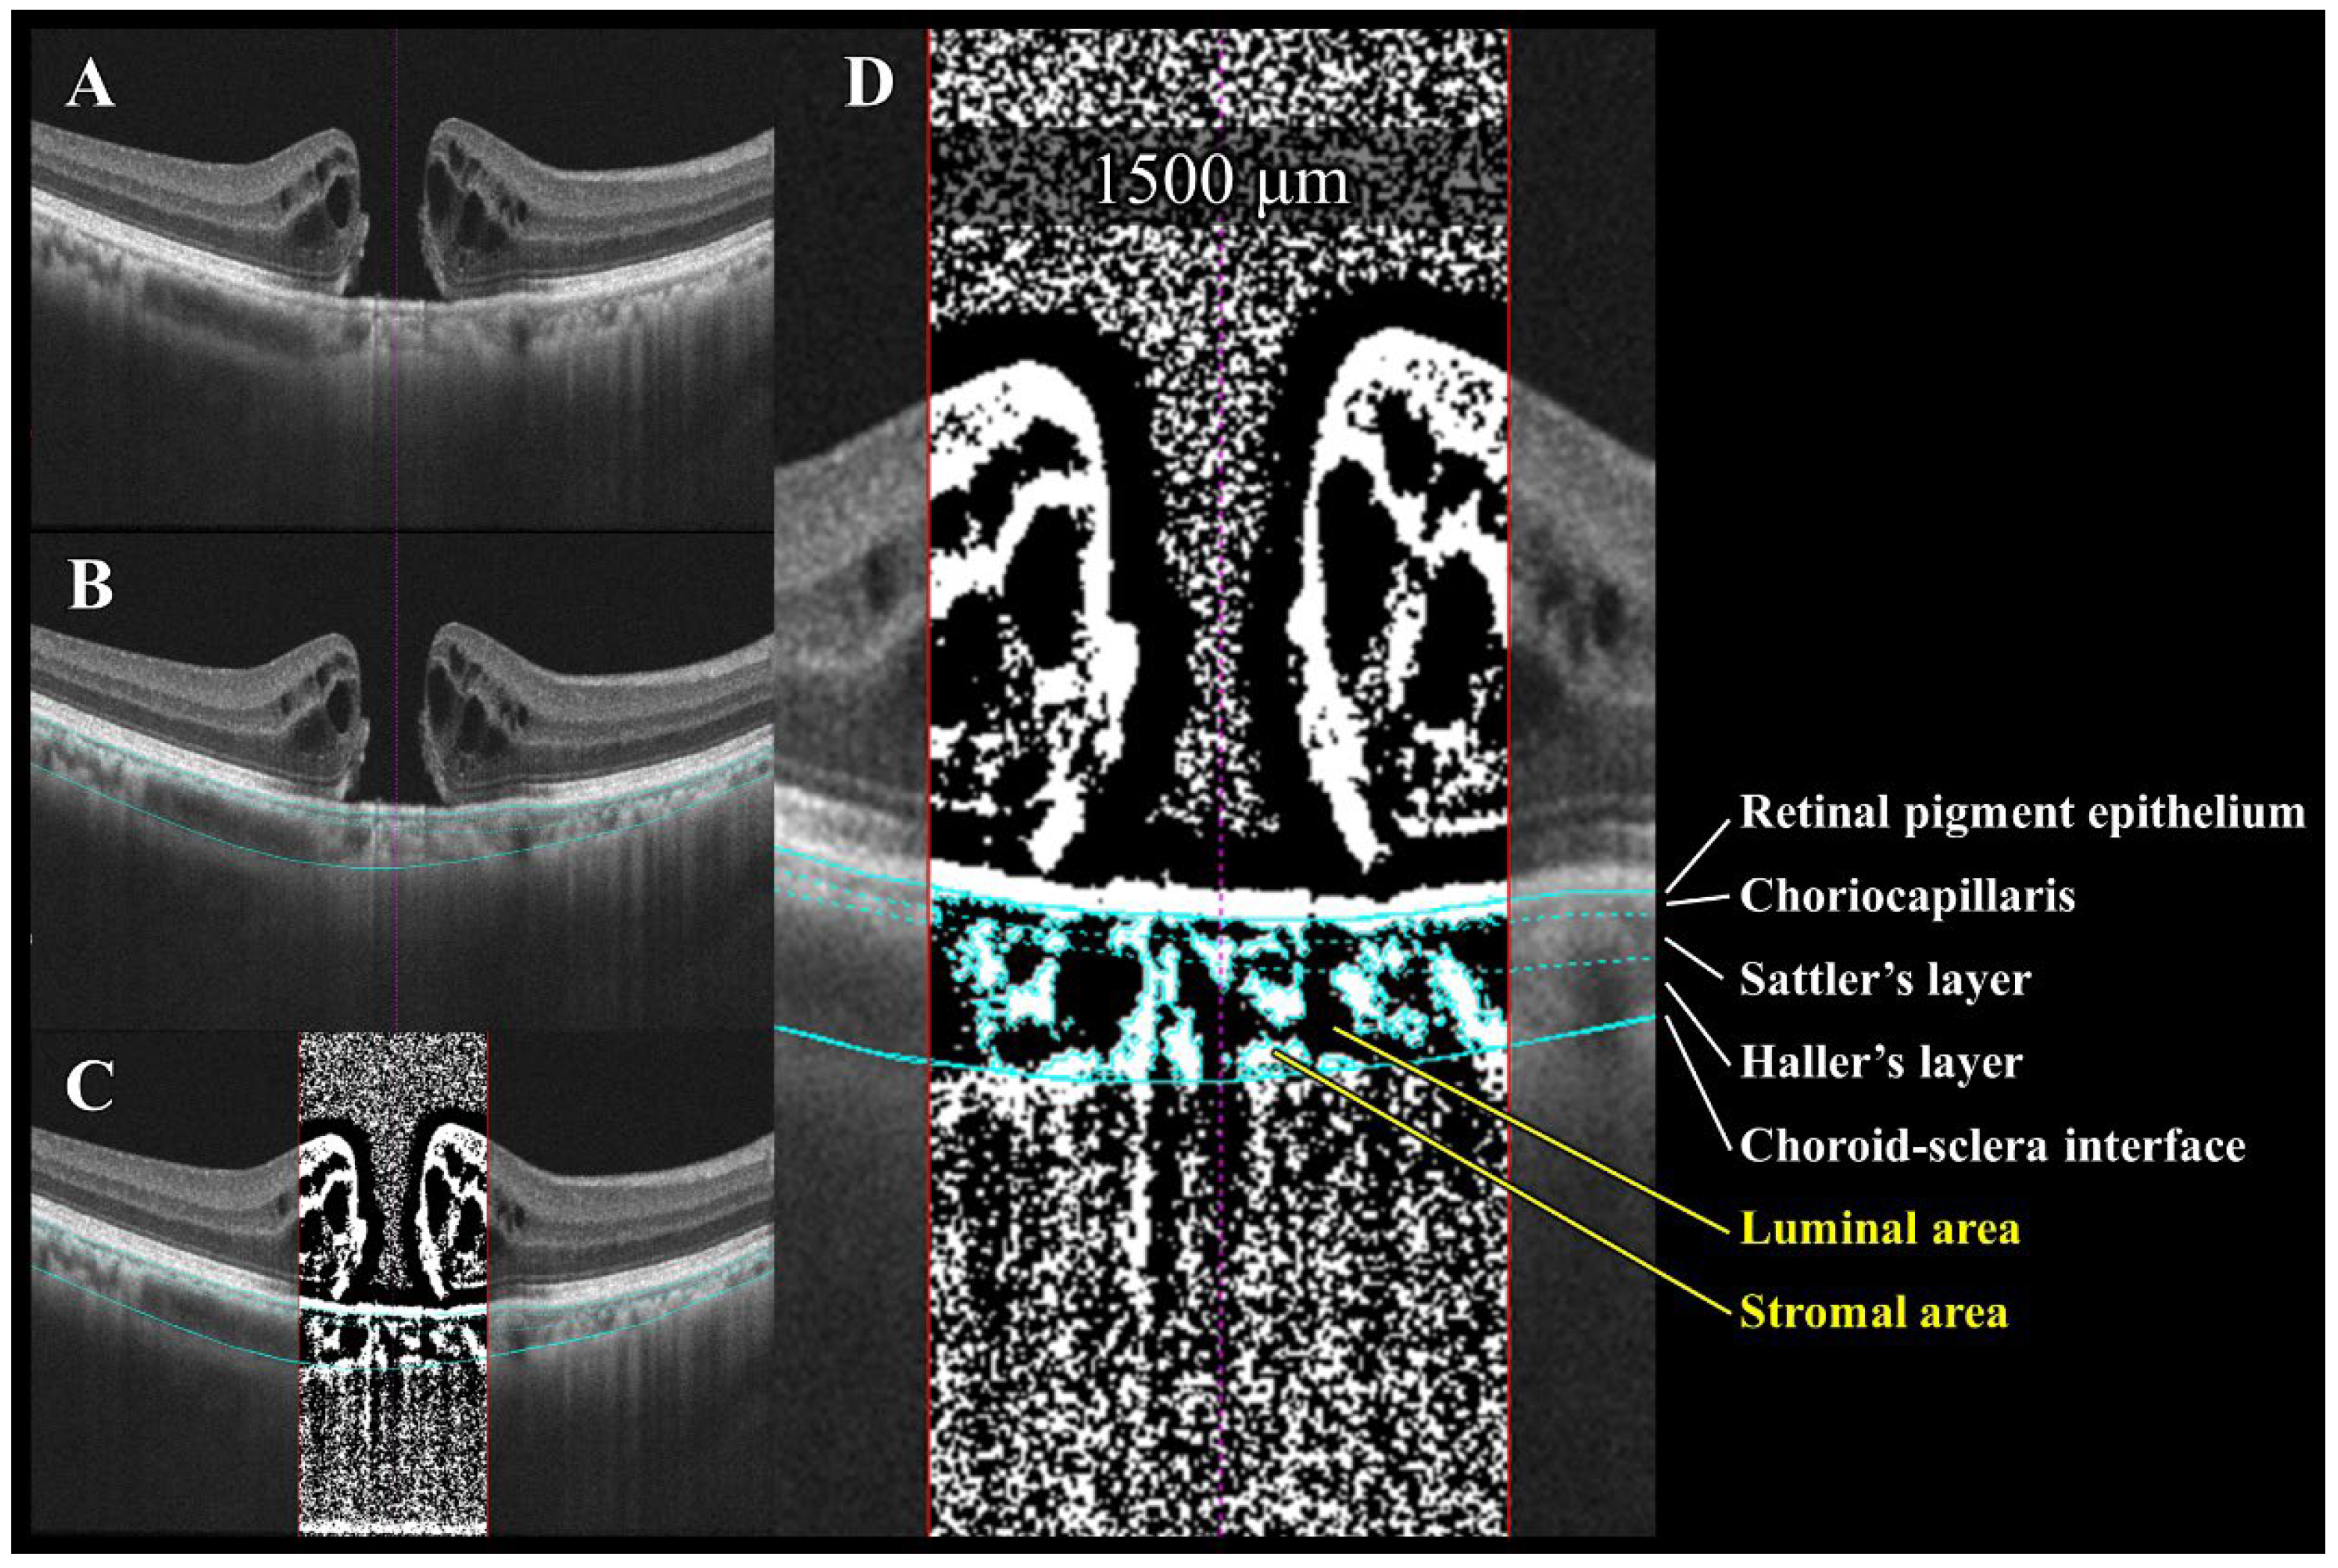

2.5. Choroidal Image Analysis Using OCT Images

The choroidal structure was assessed using established binarization methods [7,9] (Figure 3). As detailed previously [7,9], the EDI-OCT images were imported into Kago-Eye2 software, and a 1500 μm wide region centered on the fovea was delineated. The choroidal boundaries were manually identified, followed by a semi-automated segmentation of the choriocapillaris, and Sattler’s and Haller’s layers. The binarized images yielded measurements of choroidal area (CA), luminal area (LA), stromal area (SA), and central choroidal thickness (CCT). Bright pixels corresponded to the SA and dark pixels to the LA. The L/C ratio was calculated as the LA divided by the CA. The choice to use a 1500 μm wide region for choroidal analysis in this study was based on two primary reasons. First, the main pathological changes in the idiopathic macular holes (IMHs) were concentrated within this range, which allowed us to accurately evaluate the changes highly relevant to the lesion. Second, this analytical range ensured consistency with prior research. By adopting the same range used in many published studies, our data can be directly compared with past findings, demonstrating the continuity of our long-term research outcomes. All the measurements in this study were performed independently by two researchers (H.E. and Y.I.). To assess the inter-grader agreement, we used the intraclass correlation coefficient (ICC) and Bland–Altman analysis. After confirming that there was no significant difference between the two sets of measurements (verified by the absence of fixed and proportional biases on Bland–Altman plots), the average of the two measurements was adopted as the final data for analysis. This method ensured the objectivity and reliability of our measurements.

Figure 3. Semi-automated choroidal binarization of idiopathic macular hole (IMH) with bumpy border. (A) Enhanced depth imaging optical coherence tomography (EDI-OCT) image of IMH before surgery. (B) Light blue lines delineate following interfaces from top to bottom: retinal pigment epithelium (RPE)–choriocapillaris, choriocapillaris–Sattler layer, Sattler layer–Haller layer, and choroid–sclera. (C) EDI-OCT image binarized using Niblack’s method. Dark pixels represent luminal area, while light pixels represent stromal area. (D) Quantification of luminal and stromal areas within each 1500 μm wide choroidal vascular layer and calculation of luminal/choroidal area ratio (L/C ratio).